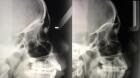

Una terapia hormonal previene la pérdida de las piezas dentales en la periodontitis